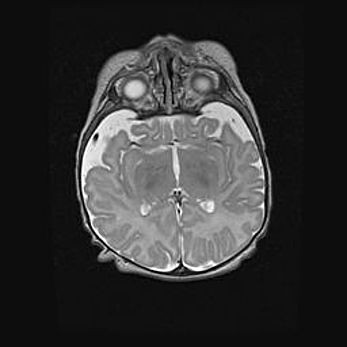

Лейкомаляция с кистозно-глиозной дегенерацией головного мозга.

Возраст: 2 месяца 25 дней

Вес: 6400 г

Окружность головы: 40 см

Срок гестации: 41 неделя

Лейкомаляцию относят к ишемически-гипоксическим повреждениям головного мозга, диагностируемым у новорожденных. При лейкомаляции в головном мозге обнаруживают очаги некроза, возникшие после тяжелой гипоксии и нарушения кровотока. В процессе морфогенеза очаги проходят три стадии: 1) развития некроза, 2) резорбции и 3) формирования глиозного рубца или кисты. Перивентрикулярная лейкомаляция (ПЛ) встречается примерно в 12% случаев среди новорожденных, обычно – у недоношенных детей, причем, частота ее зависит от массы, с которой младенец появился на свет. Наибольшее число малышей страдает лейкомаляцией, если масса при рождении 1500-2500 г.